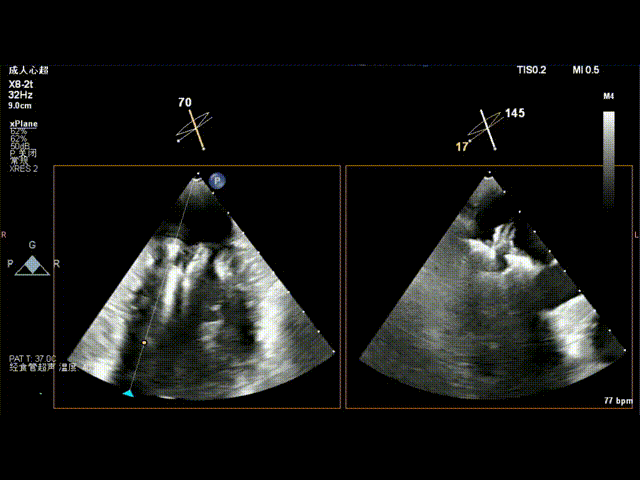

术前食道超声示: 二尖瓣2区前叶大范围脱垂伴后叶栓系。

术前食道超声-2D血流

术前食道超声-3D血流